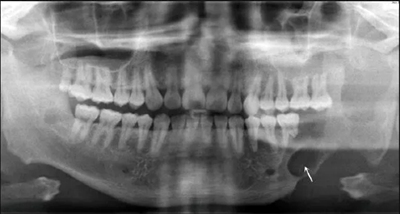

患者2014年6月5日因左下頜腫脹伴觸痛到青島大學(xué)附屬醫(yī)院口腔頜面外科就診,診斷為左側(cè)下頜骨成釉細(xì)胞瘤。全景片示左側(cè)下頜第二前磨牙遠(yuǎn)中至乙狀切跡處可見多房低密度影,左下頜第一磨牙遠(yuǎn)中根可見明顯吸收(圖1)。